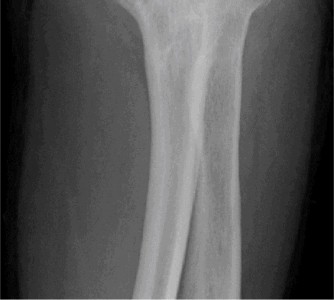

Appreciate that the outcome of calcific tendonitis is typically favorable with conservative measures? CASE 31 Dr. Robert J. Stewart A 29-year-old, left-hand-dominant male presents to clinic complaining of left arm and shoulder pain for the last three days. The patient is an avid weight-lifter and was doing the bench press when his arm began to bother him. He has been using ice and resting with mild relief but has not been able to use his left arm for anything more than carrying light-weight objects. He is also having difficulty with simple activities such as putting on his shirt. On physical examination, the patient has ecchymosis and a prominent cord-like structure on the anterior left axilla. He has significant weakness with left shoulder adduction and internal rotation. He has a negative Hawkins sign and a negative Yergason sign.

The correct answer is (B). A pectoralis major muscle (PMM) tear or rupture usually occurs in weight-lifters while performing the bench press, but it can occur during

any activity in which the arm is extended and externally rotated while under maximal contraction (eccentric loading force). Patients often present with pain, swelling, ecchymosis, weakness and loss of the axillary fold in the acute setting. In the chronic setting, the swelling and ecchymosis have typically subsided. They may report an audible pop or a tearing sensation. On examination, there can be an apparent continuous muscle or tendon that is mistaken for an intact PMM tendon, but this represents the fascia of the PMM that is continuous with the fascia of both the brachium and the medial antebrachial septum. This continuous fascia will examine as a cord-like structure as shown in Figure 2–78.

Figure 2–78

The sternocostal portion of the muscle is injured more often than the clavicular. A rotator cuff tear and biceps tendon injury are unlikely given the mechanism of injury and physical examination findings. In addition, this patient is young for a rotator cuff tear. Poland syndrome is the congenital absence of the PMM. Pectoralis minor muscle rupture is scarcely reported and would not have the same history and physical examination findings.